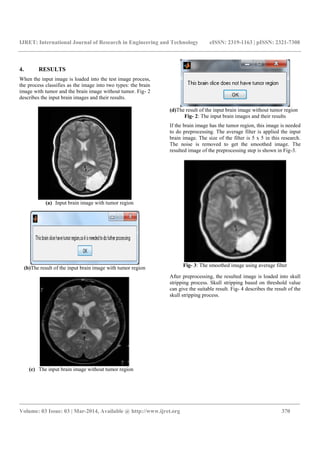

When the input image is loaded into the test image process,

describes the input brain images and their results.

(a) Input brain image with tumor region

(b)The result of the input brain image with tumor region

(c) The input brain image without tumor region

(d)The result of the input brain image without tumor region

Fig- 2: The input brain images and their results

If the brain image has the tumor region, this image is needed

to do preprocessing. The average filter is applied the input

brain image. The size of the filter is 5 x 5 in this research.

The noise is removed to get the smoothed image. The

resulted image of the preprocessing step is shown in Fig-3.